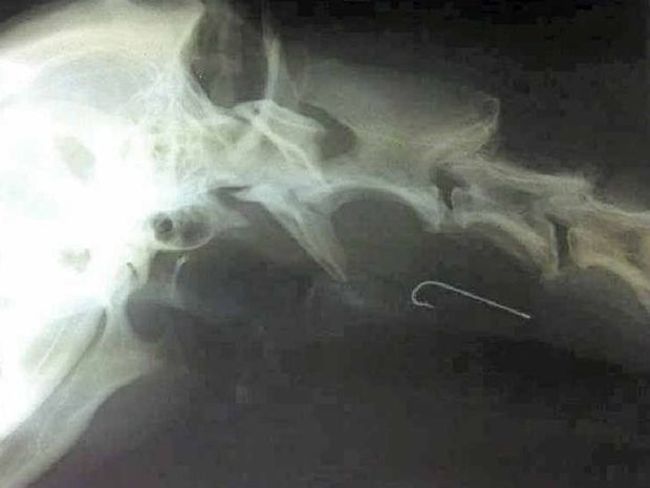

【閲覧注意】「釣り針」とかいう人体破壊兵器(画像)

gif_animation 「釣り針」とかいう人体破壊兵器…。(※ TOP画はイメージ)[18]img